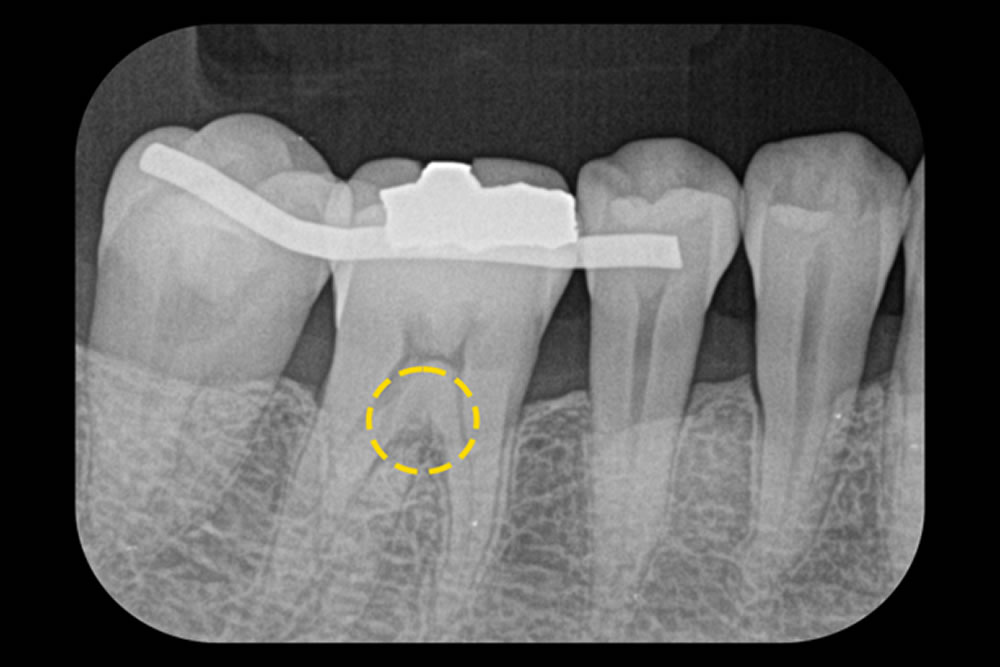

こちらの患者さまは、右下の小臼歯から大臼歯にかけて歯肉の退縮が見られ、根の分かれ目(分岐部)にも炎症が及んでいました。

歯肉退縮で、歯ぐきが下がって歯の根元が露出し、その部分に歯周ポケットが存在する状態です。見た目の変化や知覚過敏に加え、プラークが溜まりやすくなることで、歯周病の悪化につながるリスクがあります。分岐部の病変については、器具がある程度入り込む中等度の状態であり、進行すると歯の保存が難しくなることもあります。

治療では、MIST(最小侵襲手術)を行い、マイクロスコープを使用して分岐部の状態をしっかり確認しながら、Er:YAGレーザーにより感染組織を丁寧に除去。さらに必要に応じて再生療法も併用しました。歯肉退縮に対しては、セルフケアの見直しに加えて、必要であれば歯肉移植術なども検討しました。現在は、定期的なメインテナンスによって良好な状態が維持されています。